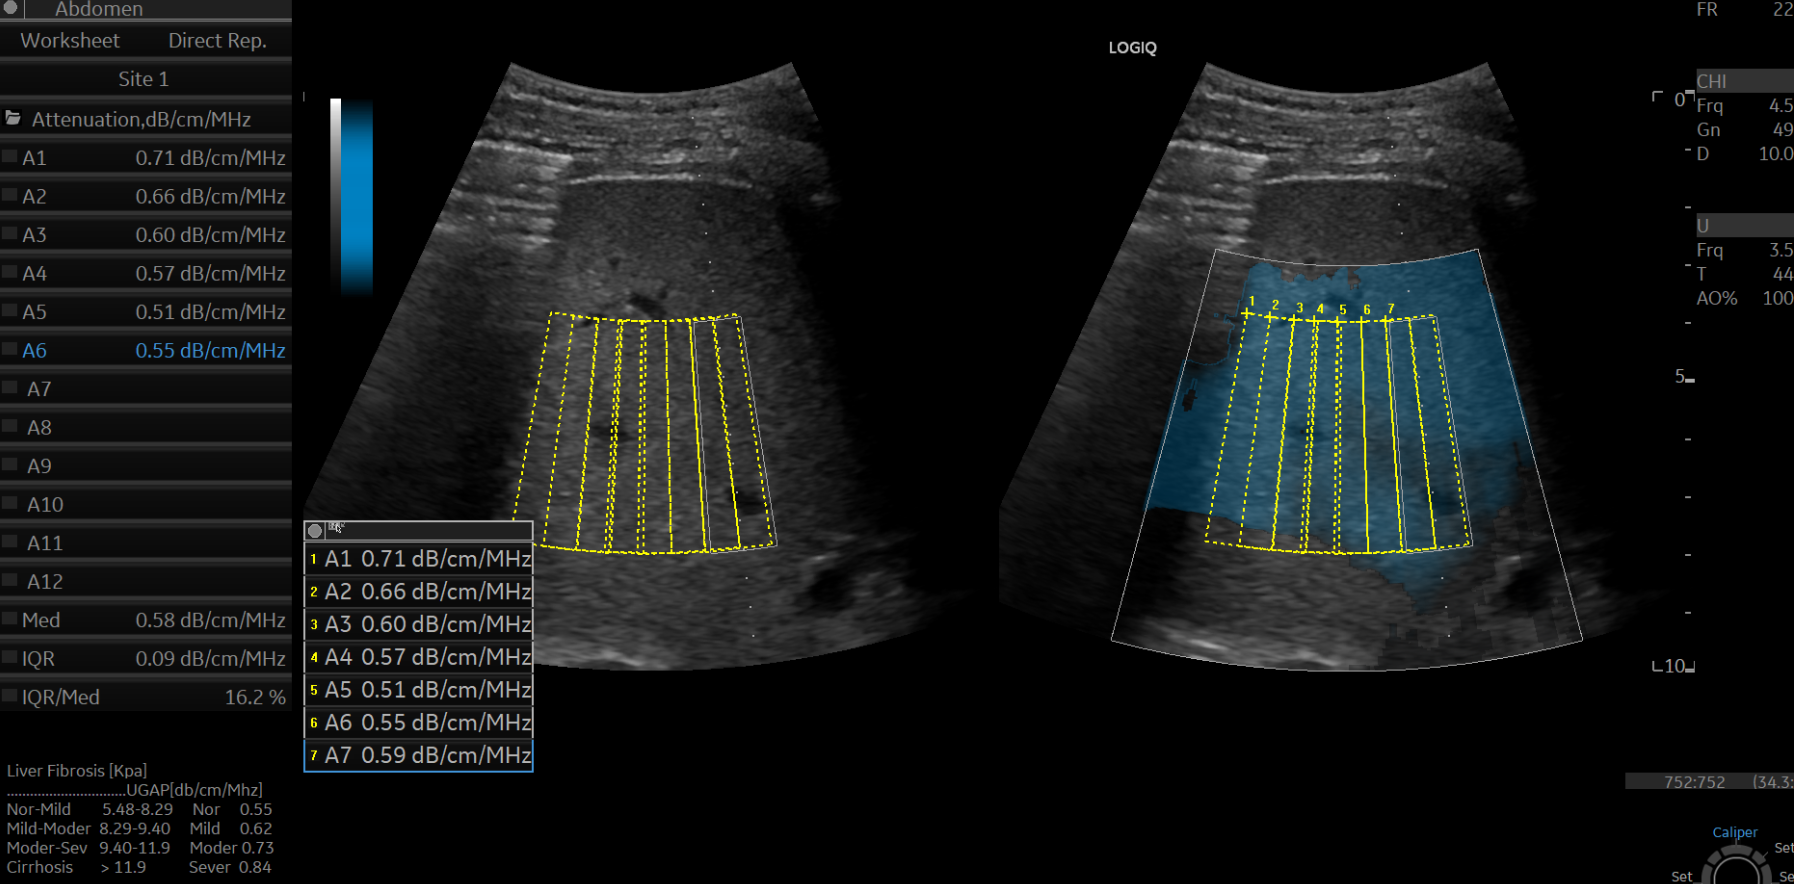

간초음파 B-mode 영상에서 거친 에코음영과 간 하연 둔화(inferior hepatic angle blunting)를 보여 전형적인 만성 간질환을 시사하고 있지만, 탄성초음파 상 탄성계수는 평균 4.3 kPa로 정상범주였으며, UGAP 정량분석에선 평균 0.58 dB/cm/MHz로 마찬가지로 정상범주 내였습니다.